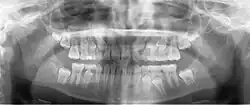

Radiografia panorâmica

A radiografia panorâmica (também chamada de pan tomografia ou ortopantomografia) é uma técnica que produz uma única imagem tomográfica das estruturas faciais que inclui ambos os arcos dentários, maxilar e mandibular, e suas estruturas de suporte. Essa é uma variante curvilínea da tomografia convencional e também se baseia no princípio de movimento recíproco da fonte de raios X e de um receptor da imagem ao redor de um plano ou ponto central, denominado plano de corte, no qual se localiza o objeto de interesse. Objetos em frente ou atrás desse plano de corte não são visibilizados de forma clara em virtude do seu movimento em relação ao centro de rotação do receptor e da fonte de raios X.

Radiografias panorâmicas são mais úteis clinicamente para o diagnóstico de problemas que requerem ampla visualização dos maxilares. Exemplos comuns incluem avaliação de traumatismo, localização de terceiros molares, patologias extensas, lesões grandes conhecidas ou suspeitadas, desenvolvimento dentário (em especial na dentição mista), retenção de dentes ou ápices radiculares (em pacientes edêntulos) e anomalias de desenvolvimento. Essas funções não requerem a alta definição e o alto detalhe das radiografias intra-orais. As radiografias panorâmicas são comumente usadas como a imagem inicial de uma avaliação por permitir adequada visualização ou auxiliar na indicação de outras radiografias. As radiografias panorâmicas também são úteis em pacientes que não têm boa tolerância a exames intraorais. No entanto, quando um exame radiográfico intraoral completo é realizado em um paciente que será submetido a tratamento dentário, normalmente pouca ou nenhuma informação útil adicional é obtida através de uma radiografia panorâmica simultânea.

A principal desvantagem da radiografia panorâmica é que as imagens não apresentam um detalhe das estruturas anatômicas tão bom quanto o das radiografias periapicais intra-orais. Portanto, as radiografias panorâmicas não são tão úteis quanto radiografias periapicais para a detecção de pequenas lesões cariosas, detalhes das estruturas periodontais ou doença periapical. As superfícies proximais de pré-molares também normalmente se sobrepõem. Logo, a disponibilidade da radiografia panorâmica em um paciente adulto comumente não exclui a necessidade de radiografias intra-orais para o diagnóstico das patologias odontológicas mais comumente encontradas. Outros problemas associados à radiografia panorâmica incluem ampliação desigual e distorção geométrica ao longo da imagem. Ocasionalmente, a presença de estruturas sobrepostas, como a coluna cervical, pode mascarar lesões odontogênicas, particularmente na região de incisivos. Além disso, objetos clinicamente importantes podem estar situados fora do plano focal (plano de corte) e podem aparecer distorcidos ou não aparecer.